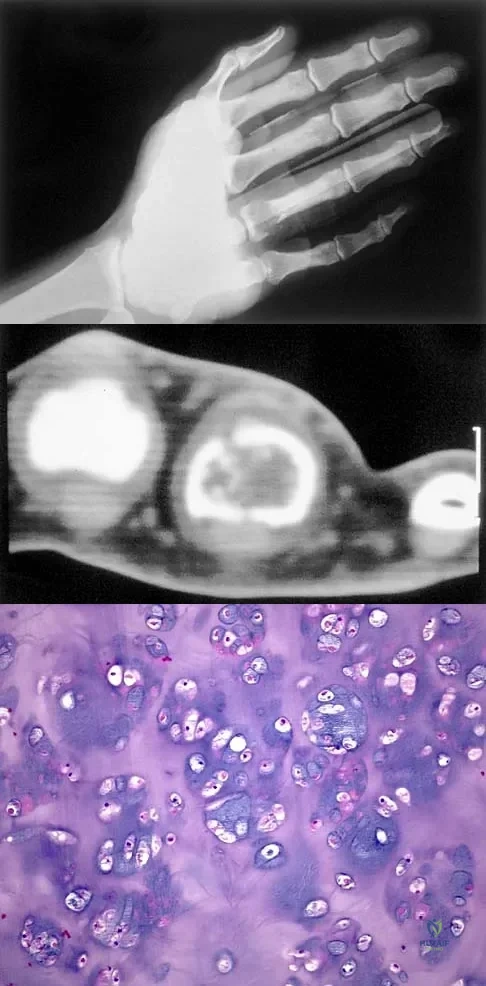

Question 55

A 30-year-old woman has pain in her right hand. The radiograph, CT scan, and biopsy specimen are seen in Figures 38a through 38c. What is the most likely diagnosis?

Explanation